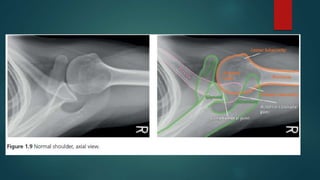

Skeletal X ray anatomy ,colour description, Imaging anatomy of musculoskeletal X rays, Diagnosis imaging anatomay, Radiology